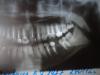

Viveya Опубликовано 8 июля, 2012 Автор Поделиться Опубликовано 8 июля, 2012 Вот Ссылка на комментарий

Scrabble Опубликовано 8 июля, 2012 Поделиться Опубликовано 8 июля, 2012 Не исключено, что стираемость есть, или клиновидные дефекты, или всё вместе, потому что колоссальное количество невитальных зубов-и всё восстановлено пломбами. Ссылка на комментарий